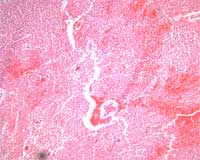

The placental histology of the dividing membrane confirmed a monochorionic diamniotic twin gestation (Figure 3 shows dividing membrane roll with back-to-back amnions and no chorion). There was also a possible acute/recent twin-twin transfusion from Baby “A” to Baby “B” (our patient). The villi from disc “A” were edematous (Figure 4), and those from disc “B” were congested (Figure 5).

Figure 4

Figure 5